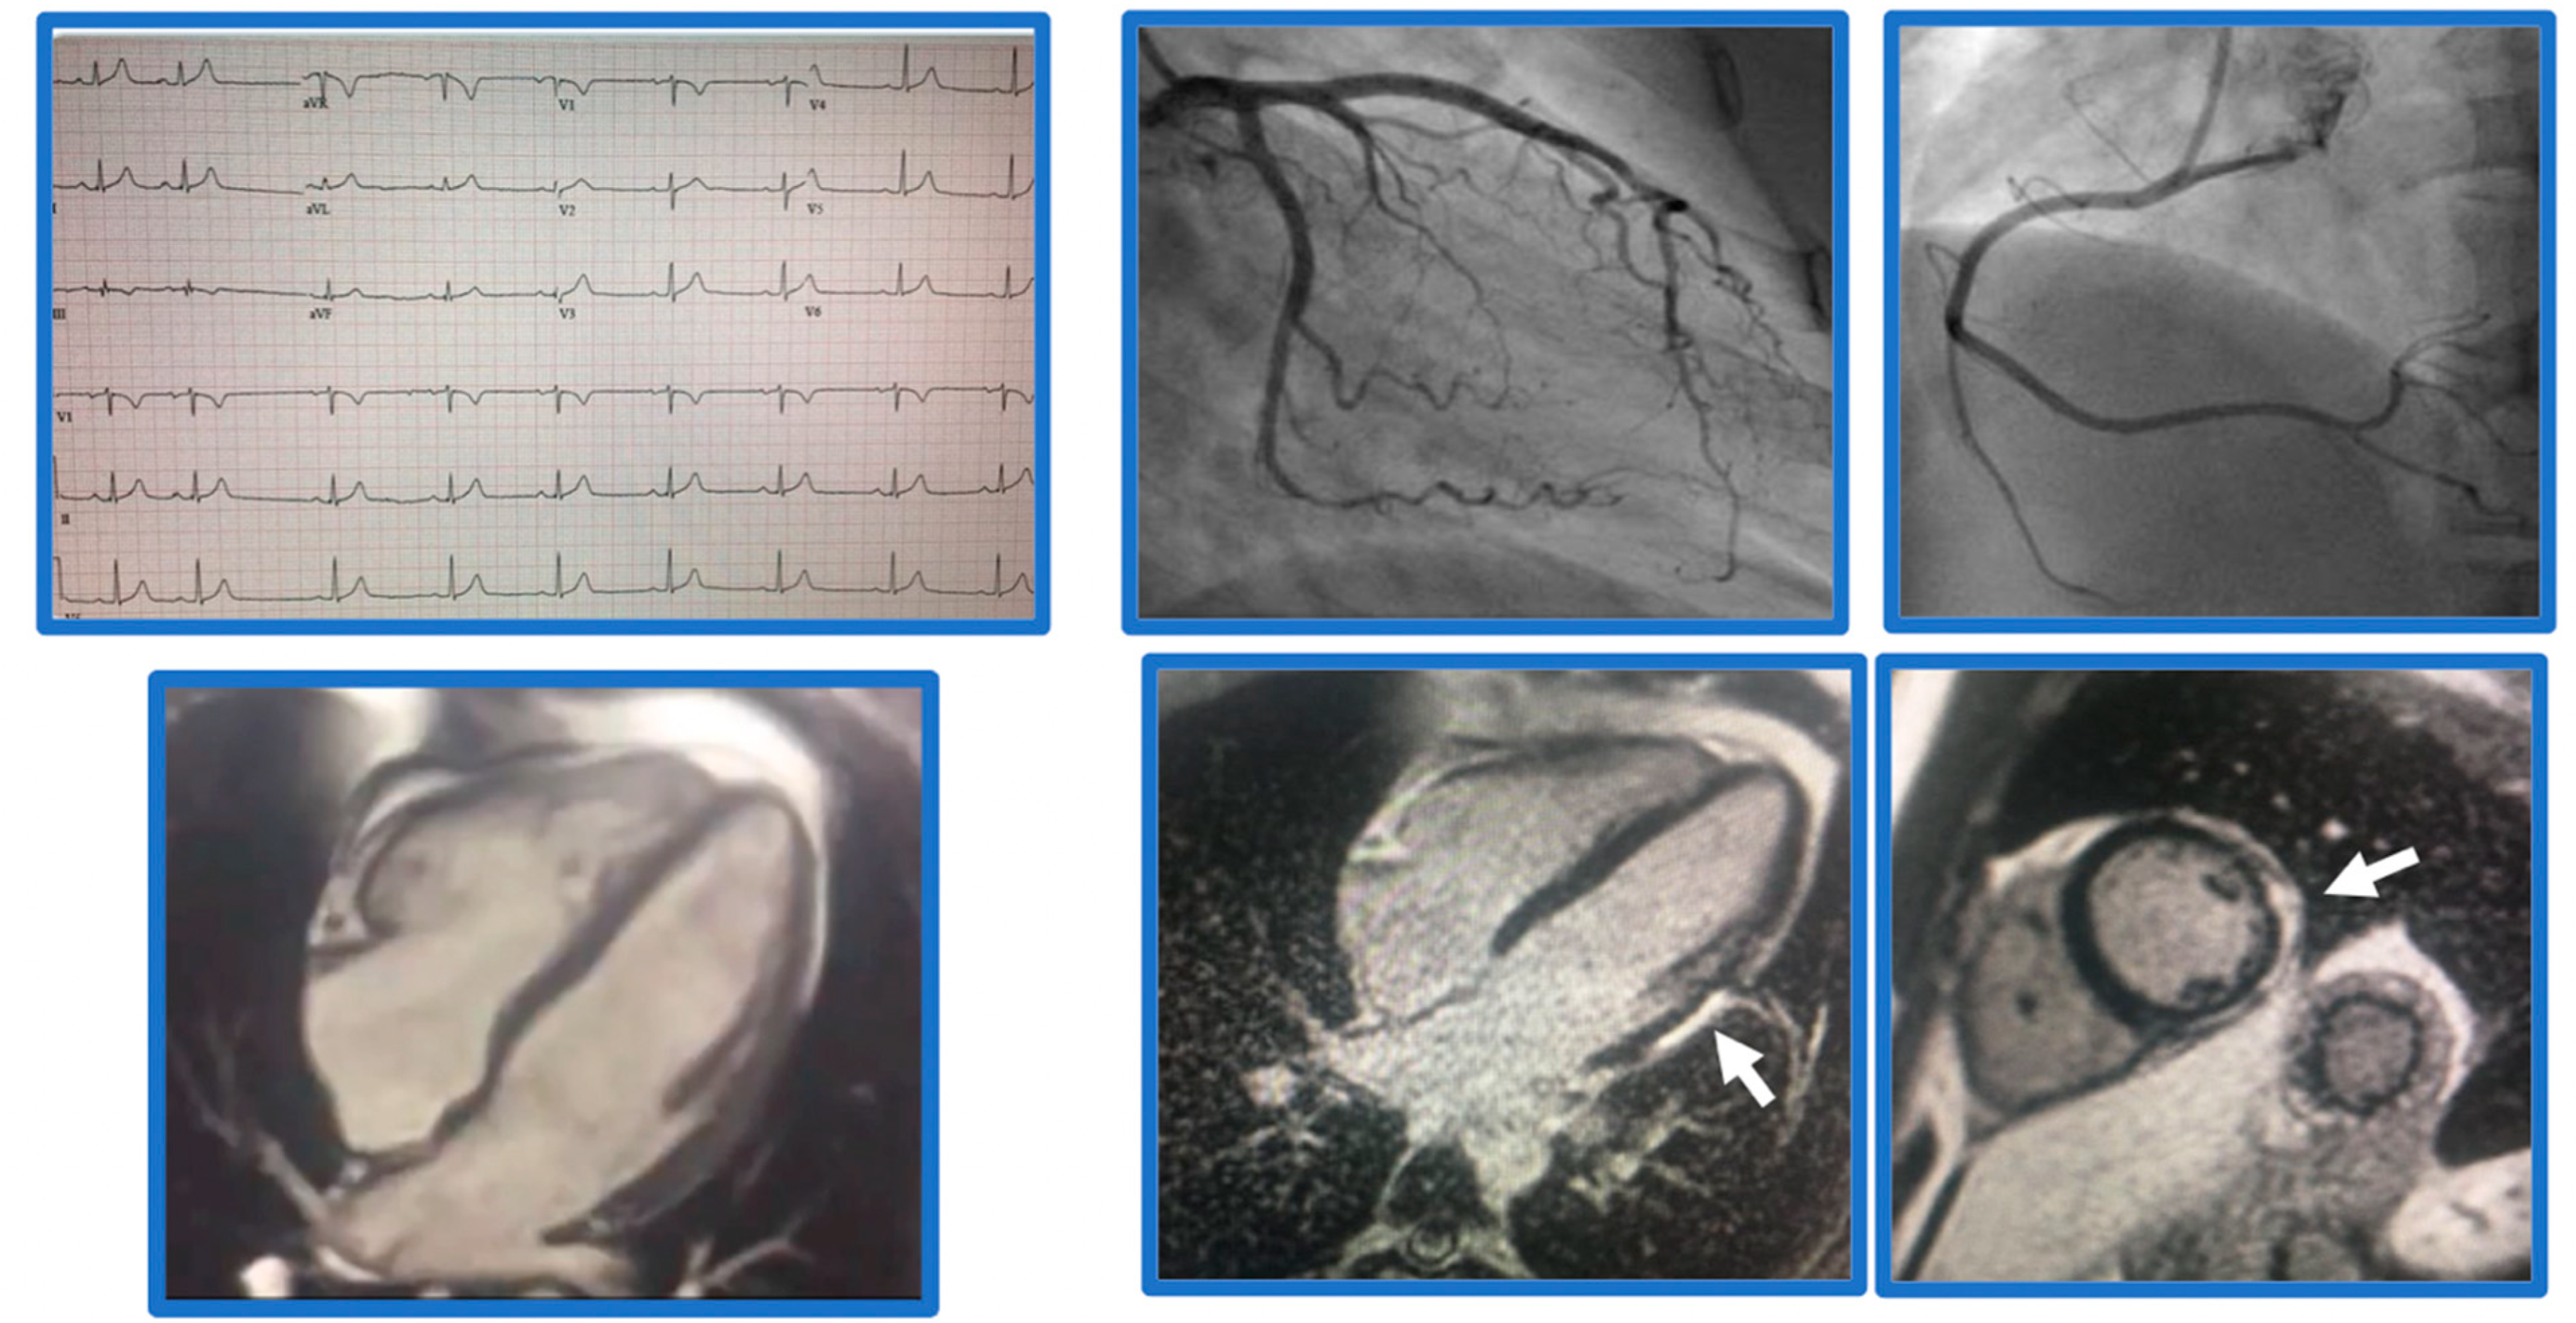

5. Myocarditis

6. Acute MI

7. Stress-Induced Cardiomyopathy